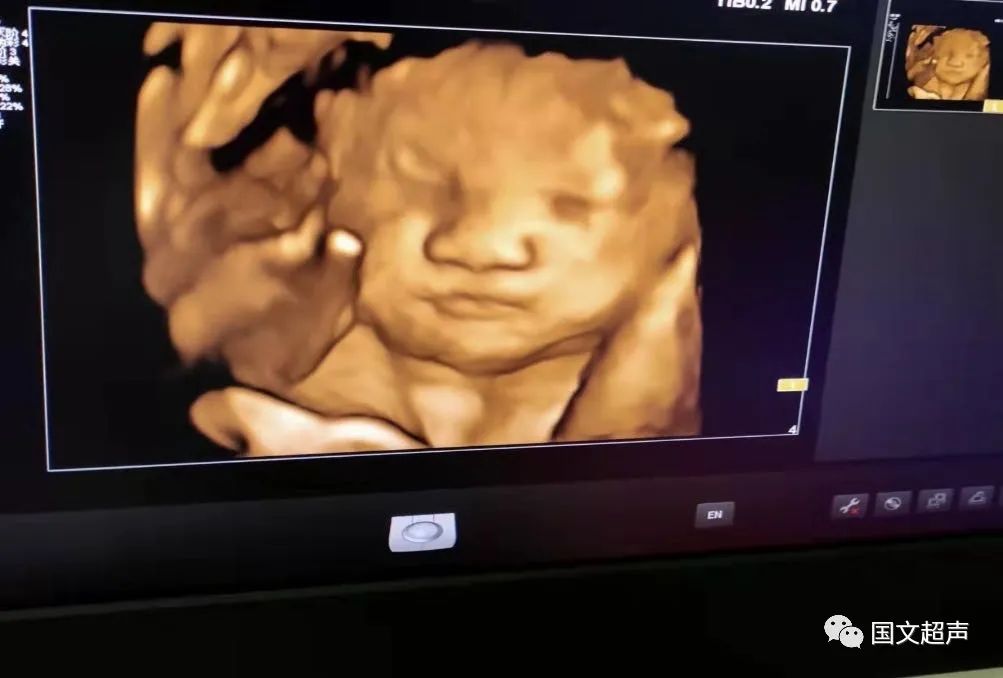

一.飛利浦EPIQ7高端四維彩超

我院目前使用的是飛利浦EPIQ7高端四維彩超,它擁有高品質自動成像分析技術,分辨率及清晰度高,可以較清晰的顯示宮內胎兒的生長發(fā)育情況,為診斷胎兒先天性畸形,如唇裂、脊柱裂、顱腦發(fā)育異常、骨骼發(fā)育異常、心血管畸形等提供準確的科學依據。